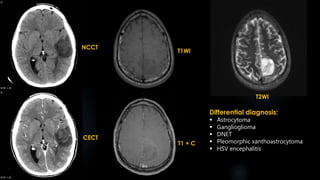

CECT T1WI

FLAIR T2WI

T1 + C

Differential diagnosis:

Ganglioglioma

DNET

Oligodendroglioma

Desmoplastic infantile

NCCT

CECT

T1WI

T2WI